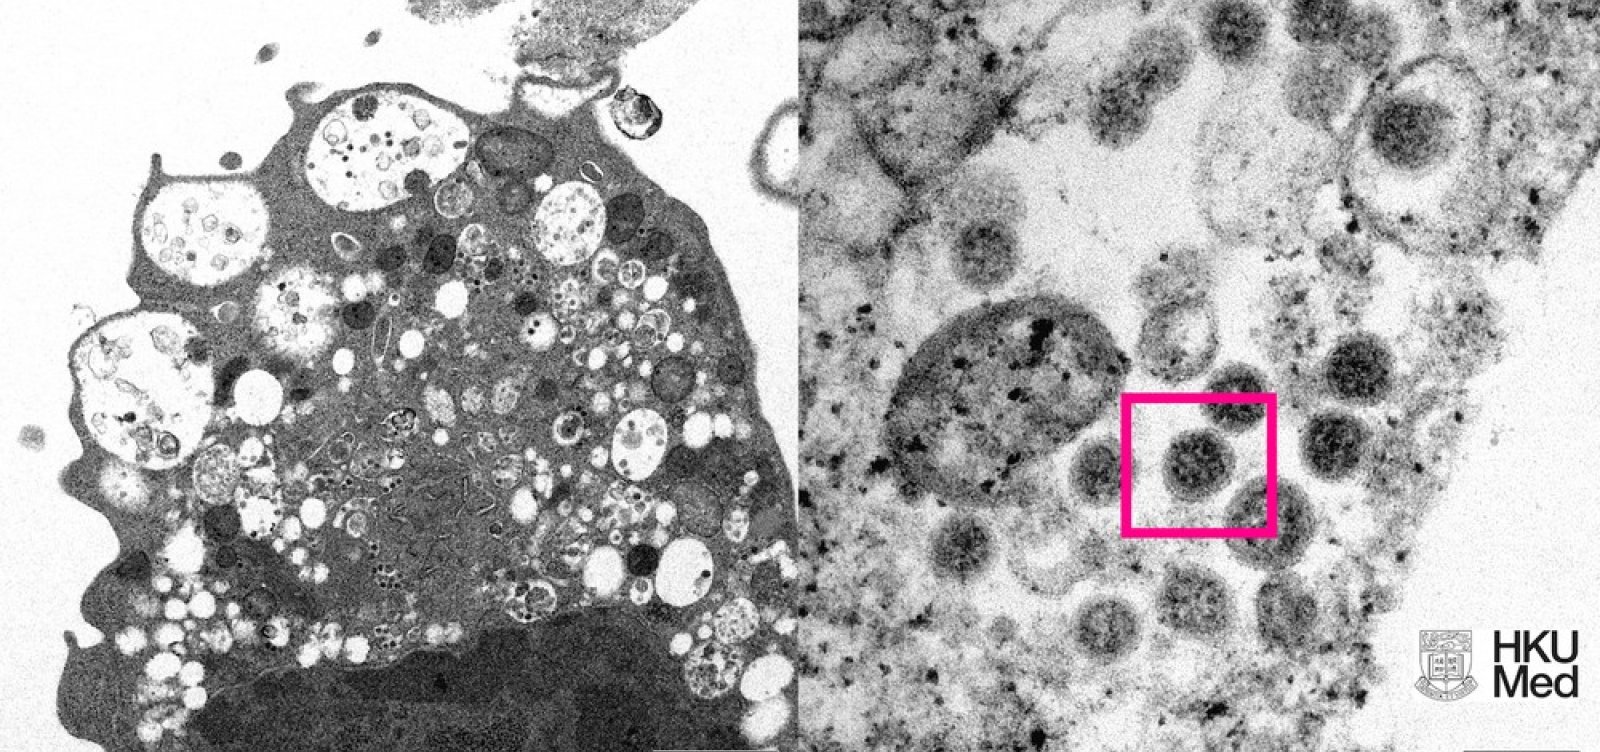

Foto: Cortesia Faculdade de Medicina da Universidade de Hong Kong